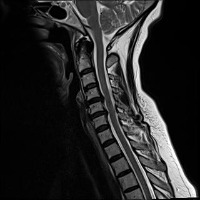

Classes (24)

Annular Disc Relaxationrotation

Annular Tearrotation

Annular disc relaxationrotation

Annular tearrotation

Degenerated discrotation

Degenerative Disc Diseaserotation

Demyelinating Plaquesrotation

Demyelinating plaquesrotation

Disc Bulgerotation

Disc Bulgerotationtrack_idkeyframe

Disc Herniationrotation

Disc Protrusionrotation

Disc Relaxationrotation

Disc bulgerotation

Disc bulgerotationtrack_idkeyframe

Disc herniationrotation

Disc protrusionrotation

Disc relaxationrotation

Fracturerotation

Hemangiomatarotation

Osteophytesrotation

annular tearrotation

diffuse disc bulge with neural compromiserotation

stenosisrotation